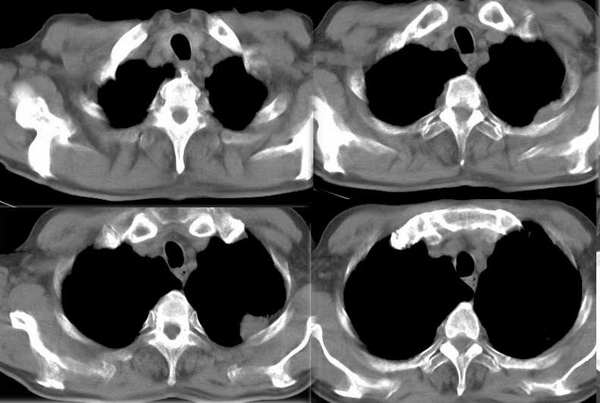

今年二月份ct检查

今天复查ct